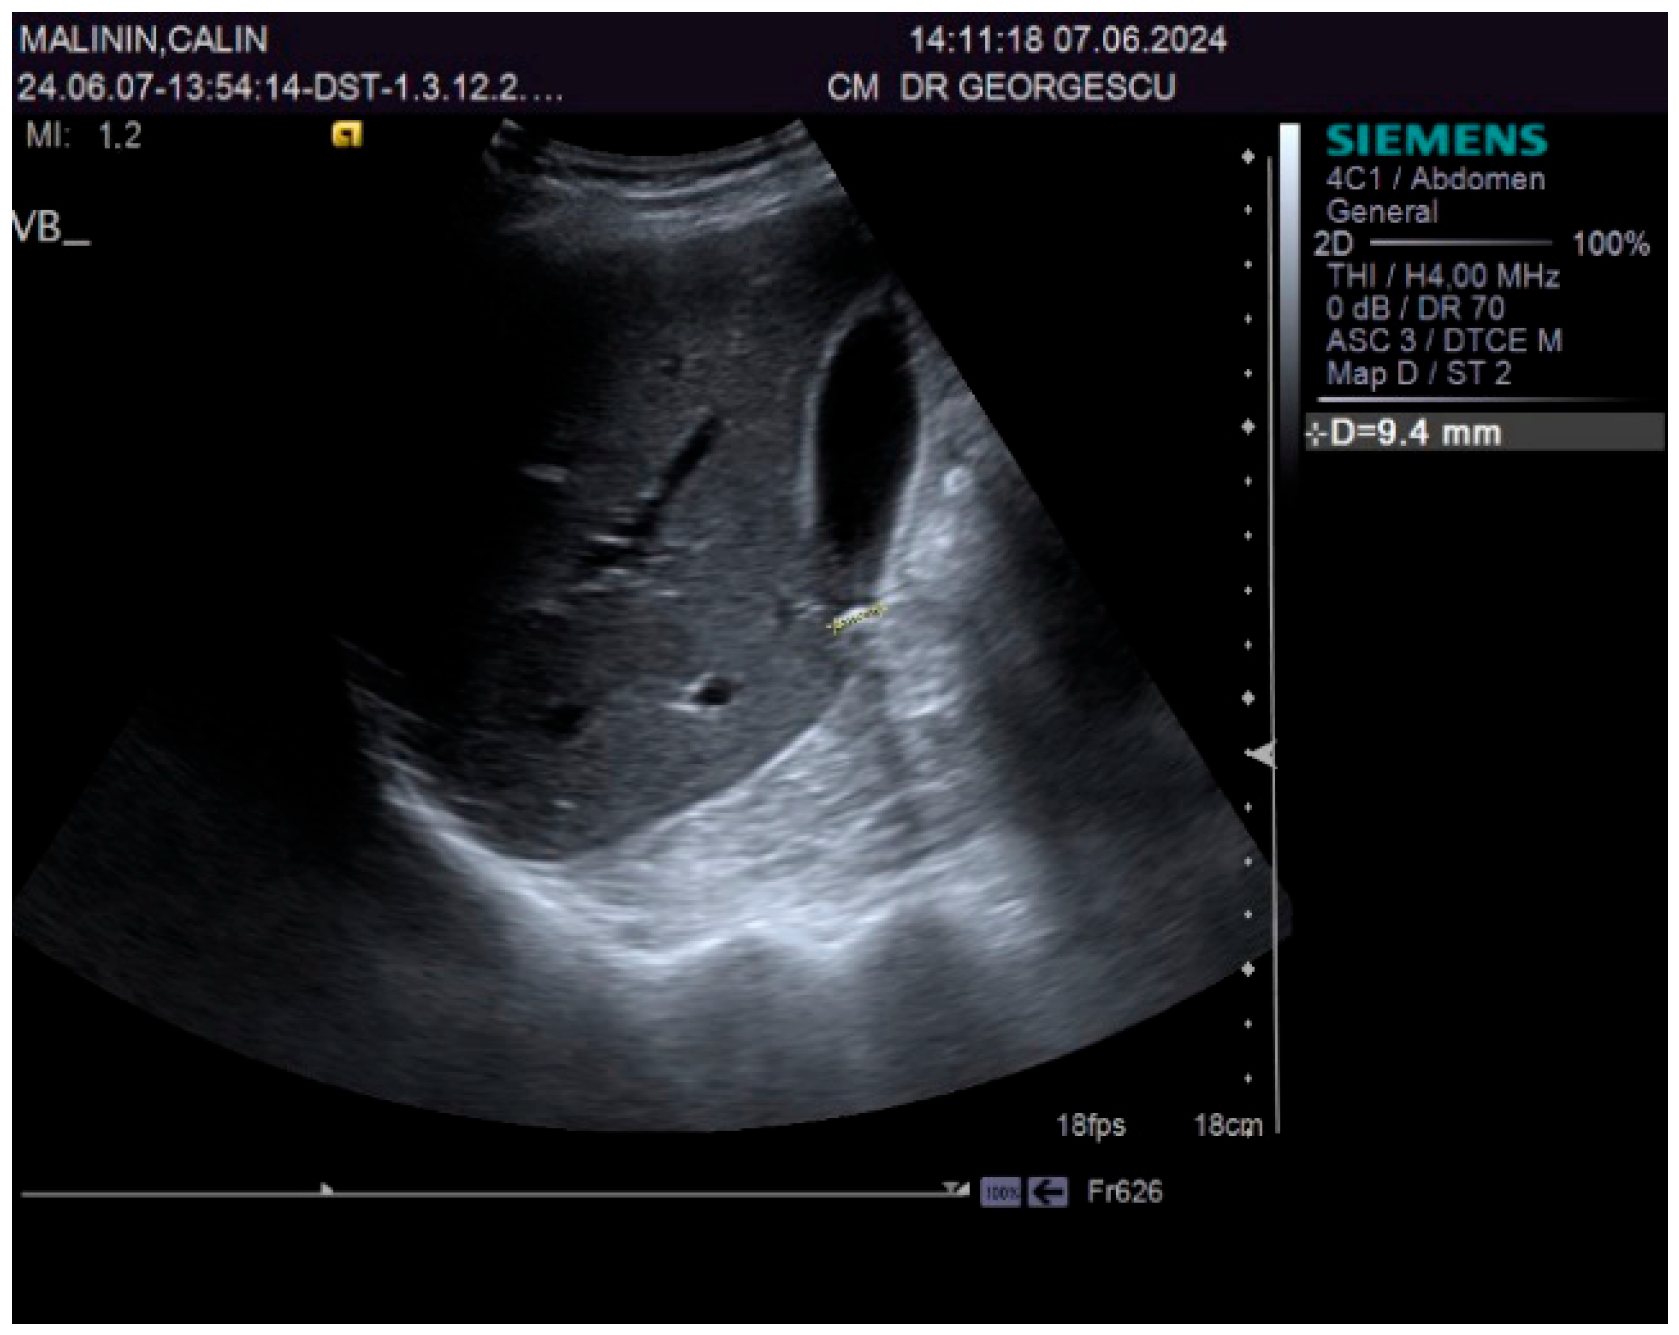

A 55-year-old male patient, complaining of recently onset, persistent generalized itching, was first examined by a dermatologist in the middle of May 2024 and no physical signs of skin disorder were found. Routine blood and stool workups were performed. No food or respiratory allergies were identified, and stool samples were negative for parasites. The recommended antihistamines were only partially effective, pruritus being present even during nights, resulting in a lowering of the patient’s quality of life. Given the mild dyspeptic-associated complaints, the patient was referred to a gastroenterological consultation on 7 June 2024 with a suspected biliary disorder. Medical history revealed no significant familial or personal pathologies, no smoking or alcohol drinking and no exposure to toxic substances. Physical examination found no particular pathological features, no peripheral palpable lymph nodes or skin lesions, normal respiratory and cardiovascular aspects, and blood pressure = 120/70 mmHg. However, the patient was overweight (BMI = 28 kg/m2) and displayed a mild palpatory tenderness of the middle and upper-right abdominal quadrant. Abdominal duplex ultrasound revealed multiple small echogenic formations adjacent to the gallbladder wall, likely cholesterol polyps. As illustrated in Figure 1 and Figure 2, two small calculi were also visualized in the infundibular zone. No biliary tree dilation was observed. Additional findings included mild liver steatosis, thickening of the stomach and duodenal walls, and a hyperechoic pancreatic texture. Aortic ectasia (2.7 cm in diameter) was noted just proximal to the distal bifurcation. No ascites or retroperitoneal lymph nodes were present.

Figure 2.

Ultrasound aspect: diffuse liver steatosis.